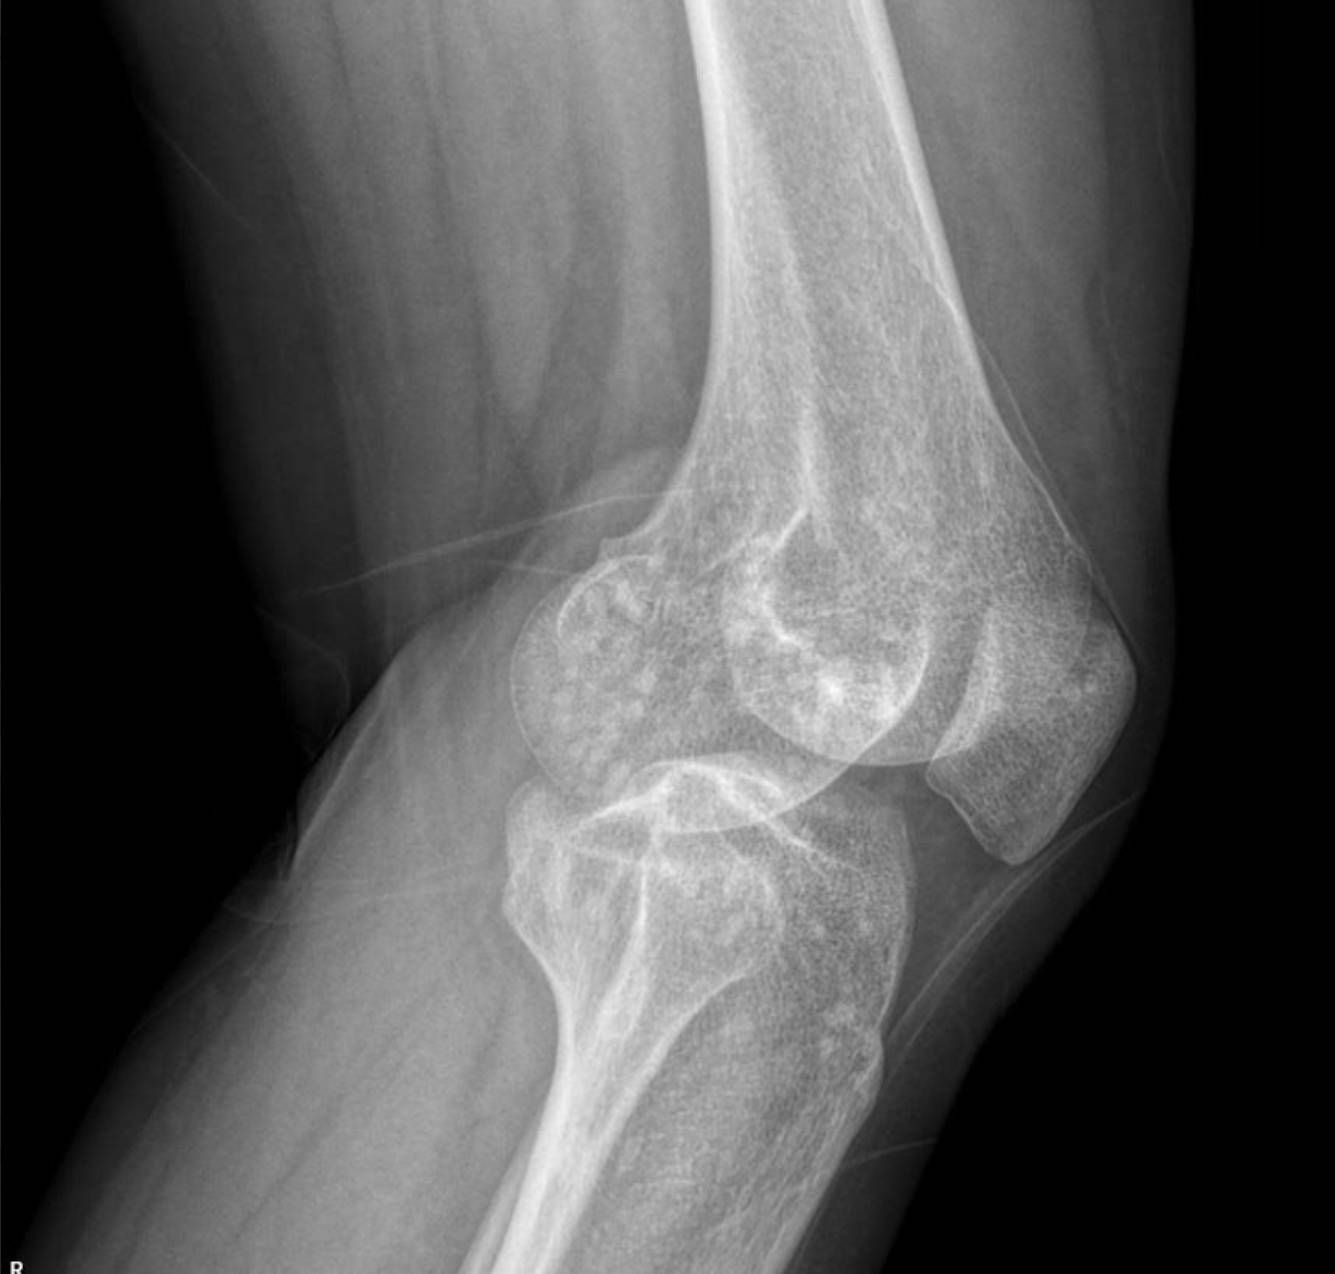

Radiological Findings: Skeletal X-rays (Incidental Discovery)

During the extensive workup for her hypertension and renal issues, skeletal X-rays were performed, which revealed a striking and unexpected finding.

The X-rays of the pelvis, knees, elbows, wrists, and ankles demonstrate multiple, discrete, well-circumscribed sclerotic (densely opaque) lesions distributed symmetrically throughout the bones. These lesions are typically ovoid or spherical, varying in size, and are predominantly located in the epiphyses and metaphyses of long bones, as well as in the carpal and tarsal bones and the pelvic girdle.

Specifically:

- Knees: Both distal femurs and proximal tibiae show widespread small, dense sclerotic foci within the epiphyses and metaphyses. The joint spaces appear preserved.

These widespread, symmetrically distributed sclerotic bone islands are pathognomonic for hereditary osteopoikilosis (also known as osteopathia condensans disseminata). This condition is typically benign and often discovered incidentally. While not directly related to her renal artery stenosis or hypertension, its discovery is crucial for patient management as it can sometimes be associated with other connective tissue disorders, though often it is an isolated finding.